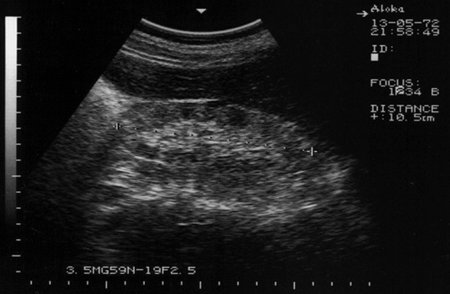

Амилоидоз почек. Renal amyloidosis

Диагноз доказан морфологически.

amyloid1.jpg